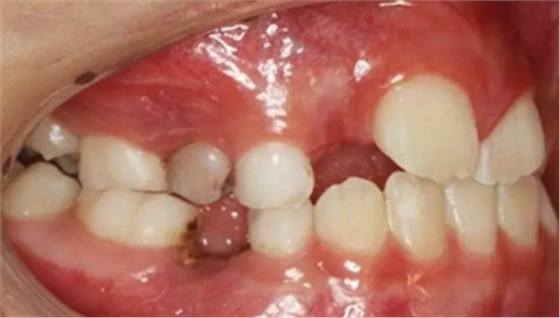

1、 患者 男 7歲 右下乳IV因齲早失

3、曲面斷層片 示恒牙萌出間隙不足